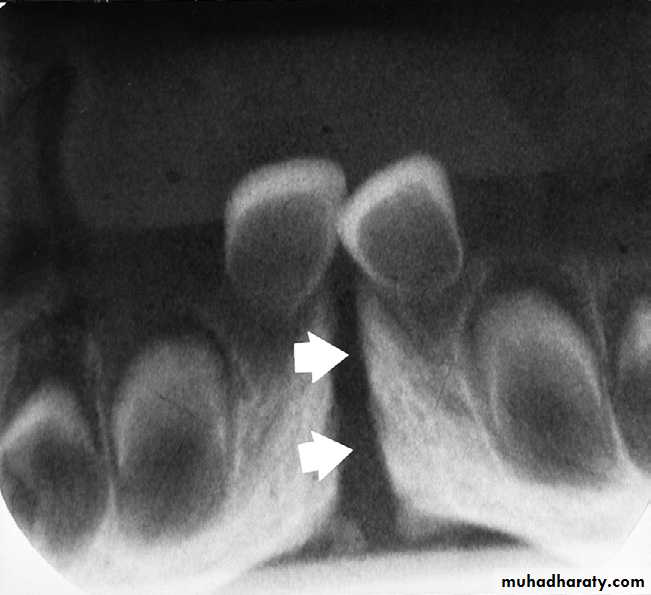

MANDIBULAR CANAL:

The mandibular canal is a tube like passage way through the bone that travels the length of the mandible, its extends from the mandibular foramen to the mental foramen and houses the inferior alveolar nerve and blood vessels. On radiograph the mandibular canal appears as a radiolucent band outlined by two thin radiopaque lines that represent the cortical wall of the canal.